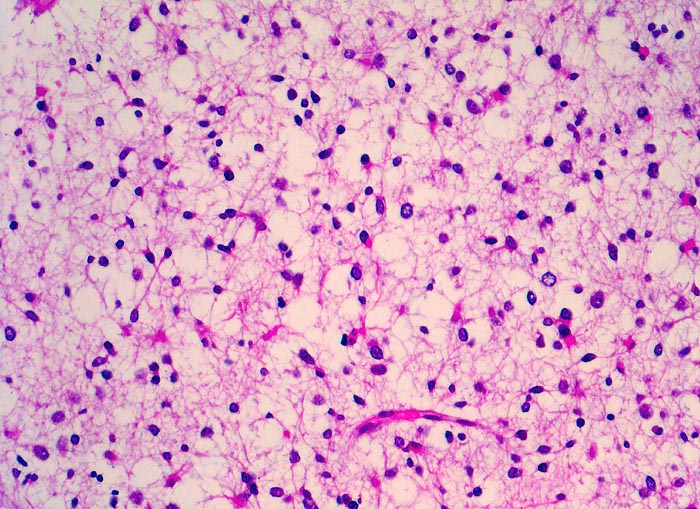

PathoPic ID 5253 - Oligodendrogliom (WHO Grad II)

Oligodendrogliom (WHO Grad II)

maligner Tumor

Hirn frontal

Nervensystem

Tumorzellen mit klarem Zytoplasma

Kopfschmerzen und epileptische Anfälle seit zwei Jahren.

Histologie

200